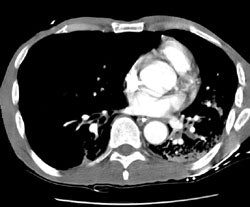

CT PE exam: Alternative diagnosis

The CT PE exam shown below demonstrates bilateral air space disease and a right pneumothorax that was not evident on the patients CXR (Click CXR to enlarge). The CT-PE exam can suggest an alternative diagnosis to explain the patients symptoms in 10-50% of cases.